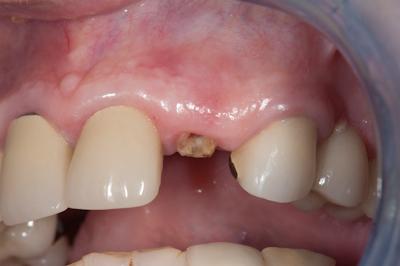

Удаление зуба под коронкой, удлинение коронковой части

Если обнаружилось, что под коронкой зуб продолжает болеть, значит, началось воспаление.

Причиной может стать попадание инфекции или киста, а также разрушение корня. Если затронут участок под десной, остаток зуба удаляется и заменяется искусственным материалом.

Если болит зуб под коронкой, и рентген показал инфекцию в корне, необходимо убирать и зуб, и коронку, особенно при удалённом нерве, и после этого ставить полноценный протез на штифте.